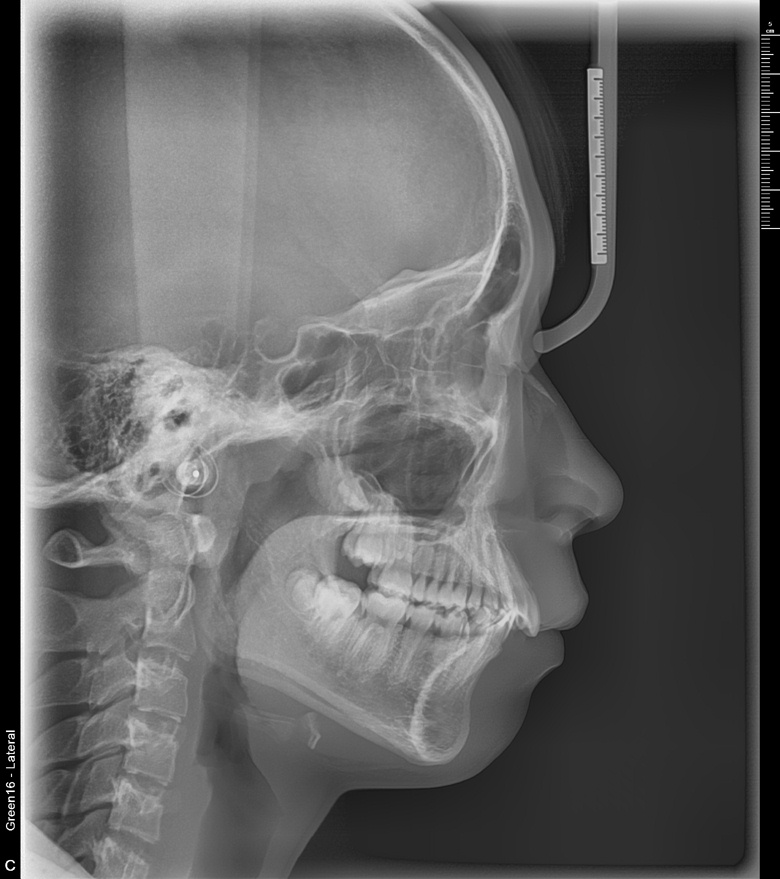

치료 후 사진입니다.